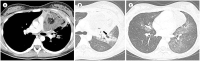

The mediastinum is the most prevalent site of extragonadal teratomas. Patients with mediastinal mature teratomas are usually young adults, and the condition does not show significant sexual differences. Mediastinal teratomas are mostly located in the anterior mediastinum. Patients are usually asymptomatic, although they can have several complications when the teratomas become large or rupture. Most mediastinal teratomas can be diagnosed using CT. Diagnosing ruptured or malignant teratomas is challenging because of their atypical clinical and radiological presentations. In this article, we describe various manifestations of mediastinal teratomas, with an emphasis on radiologic features.